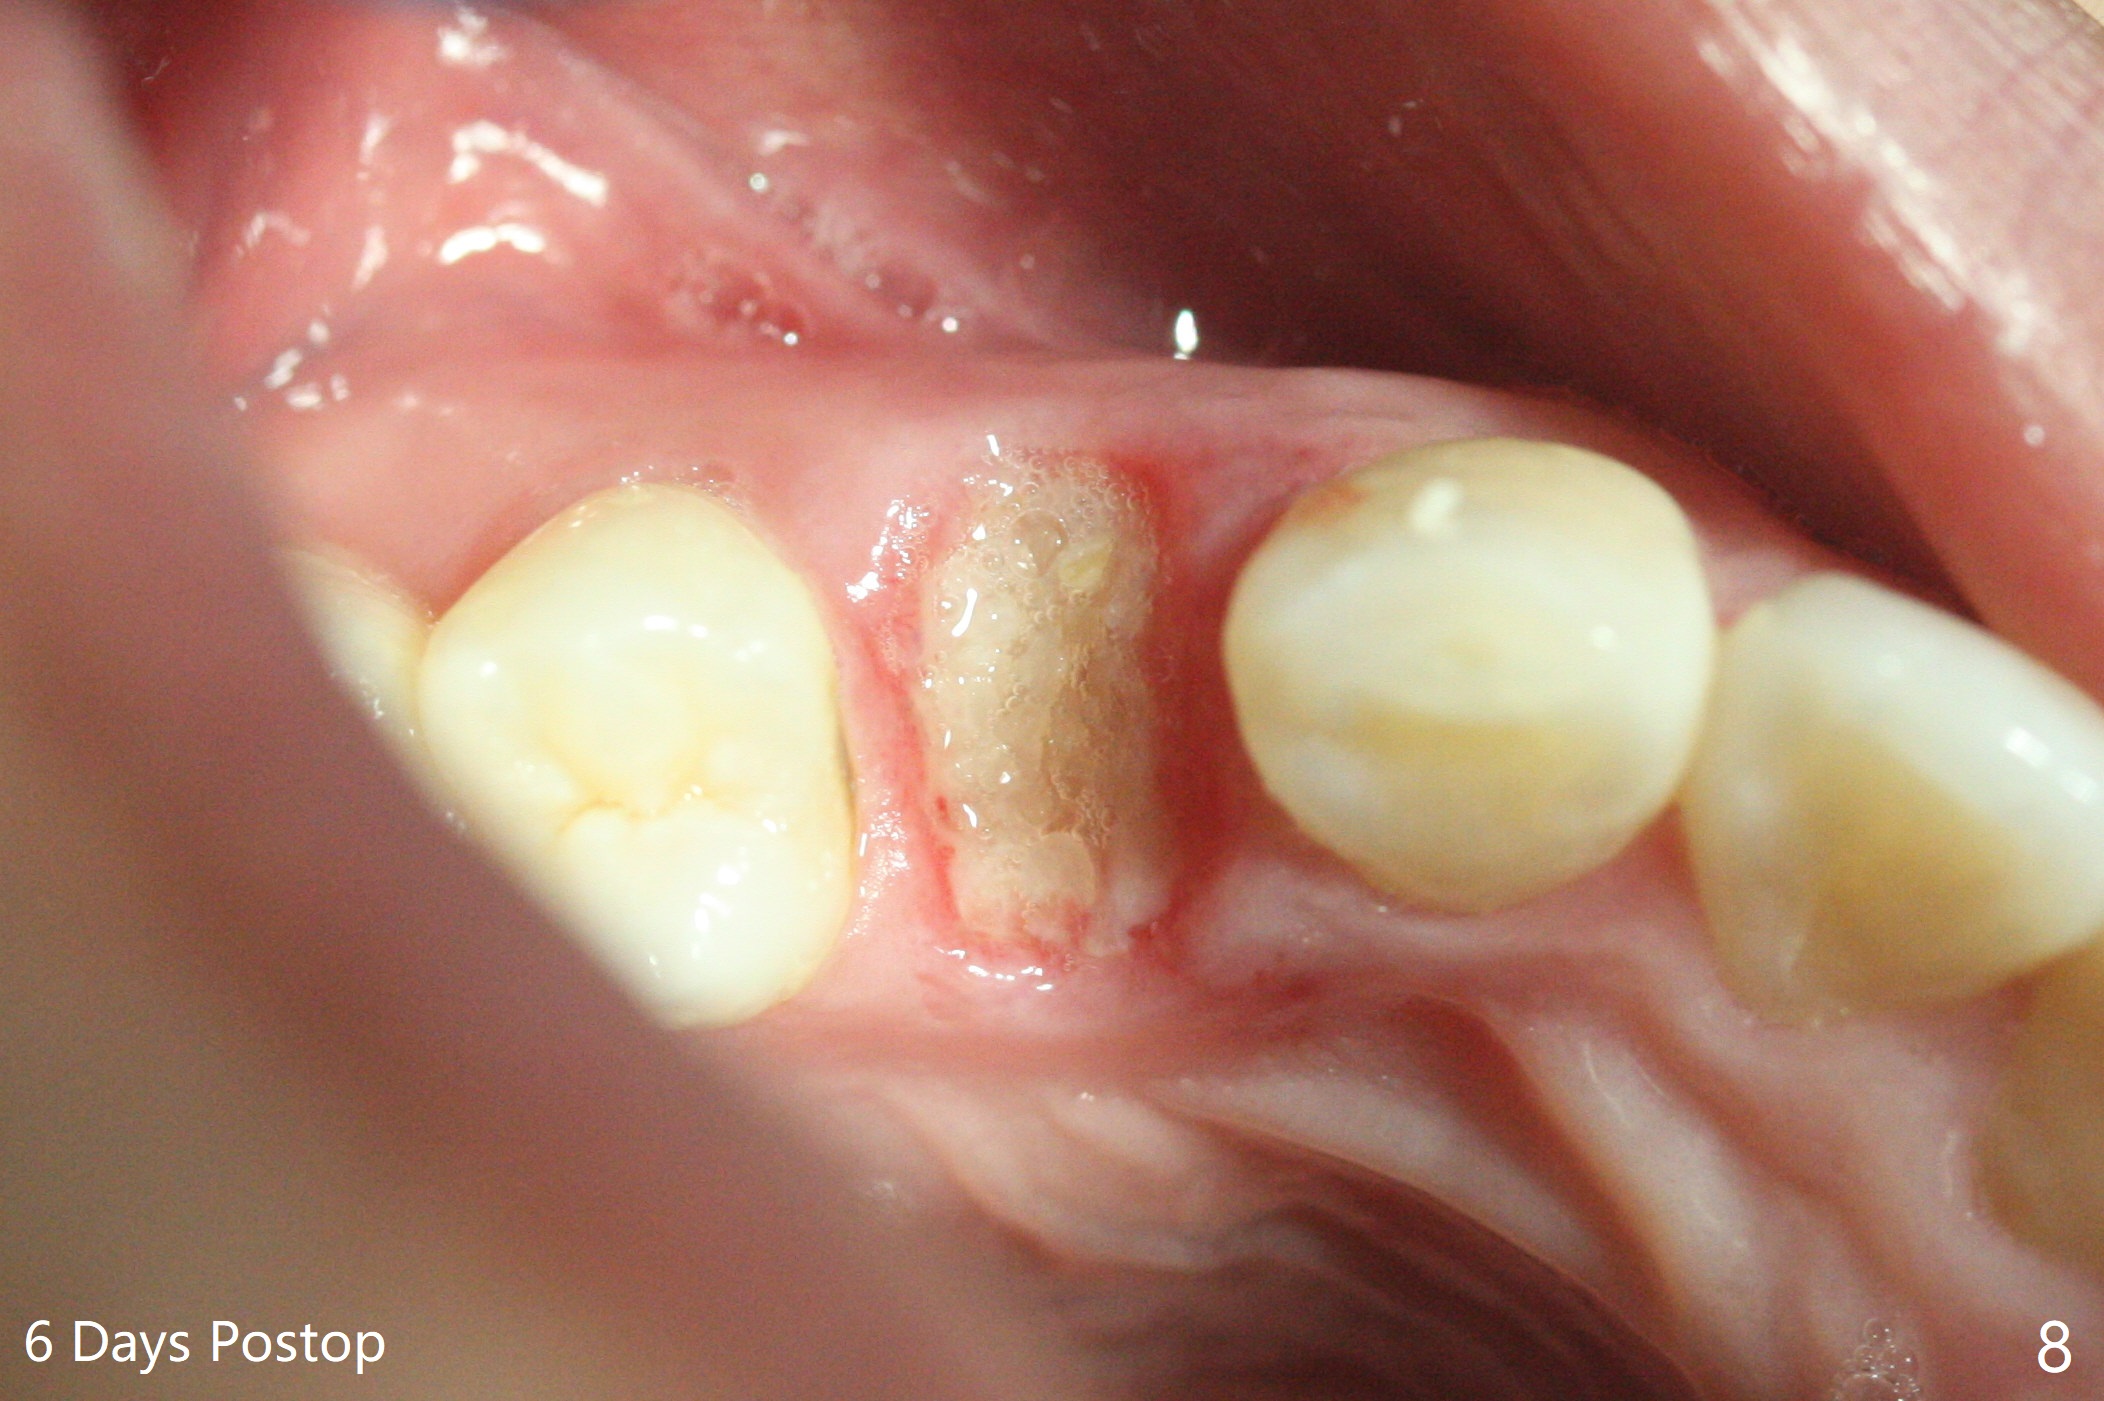

今天临床实践让我对植骨概念和操作有两方面突破,与大家分享讨论。PRF/sticky bone(粘性骨粉)以及血小板因子(成品)对软硬组织缺损修复重建无疑起到不可缺少作用。但是大多数拔牙病例并不是那么严重,放置骨粉和覆盖胶原膜足够了。为了避免费时的缝线固定胶原膜,介绍一种简易固定方法,助手可以做。31岁女不想保留严重龋坏右上4(图一至四,拍摄临床照片,与后期比较,但愿简易植骨不产生骨板塌陷),虽然术前根尖片显示根尖阴影(图四),术中没有根尖骨板缺失。估计没有严重骨板缺损,她又年轻,再生能力强,所以做简易植骨(异体骨,图五),也就是不需要PRF或者血小板因子,骨粉表面放置GEM CAP(9-12月吸收膜),由胶水固定(图六),在放置牙周敷料前,在胶原膜表面涂一层含有抗单纯疱疹病毒凡士林(图七),但愿敷料脱落时,不至于把胶原膜带下来。术后第六天,病人由于左上第二磨牙不适回来,说敷料脱落,没有不适,要求检查,其实膜也丢失(图八,九),骨粉好像挺稳定,没有做如何处理,尽管少量骨粉离开牙槽窝(<)。